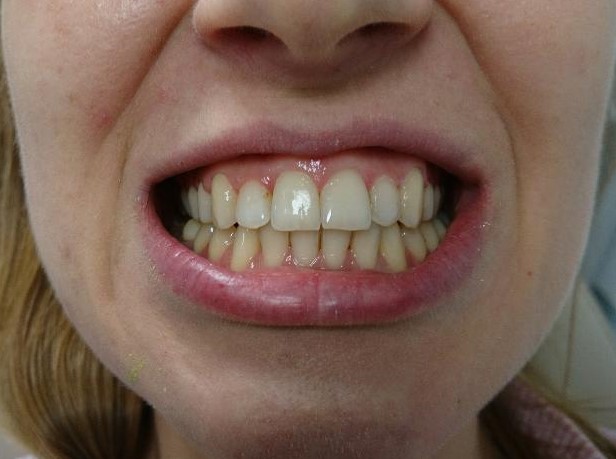

Pacient, 26 ani. Caz nonextracționist, Expander Maxilar + aparate ortodontice fixe bimaxilare.